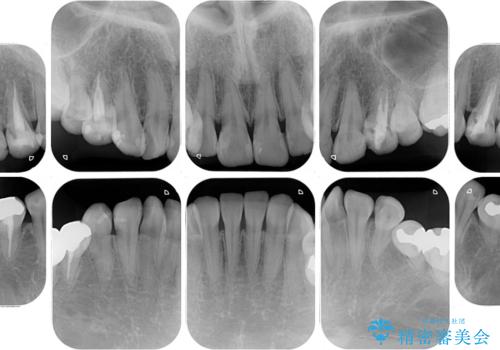

- 失活により変色した歯と不揃いな口元を気にして来院された患者様です。

口元をインビザラインにより歯列を整え、その後に失活している奥歯をオールセラミッククラウンにて補綴治療することとしました。